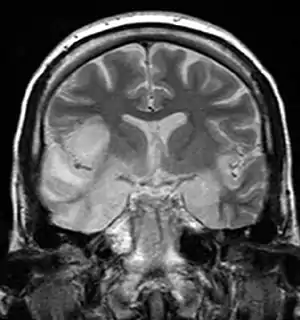

| MRI scan image shows high signal in the temporal lobes and right inferior frontal gyrus in someone with HSV encephalitis. | |